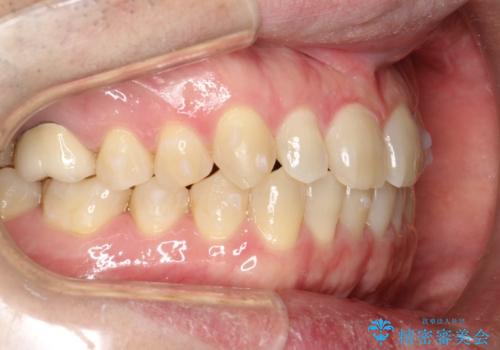

前歯の真ん中の隙間を閉じたい インビザラインによる目立たない矯正

- 上顎の正中の隙間が気になるとのことで来院されました。

下の歯と歯の間をわずかに削り、スペースを作り、正中の隙間を閉じる計画としました。

装置はインビザラインにて行いました。

インビザラインで目立たずに矯正治療を行うことができました。

使用時間を守っていただけたので、比較的スムーズに矯正を終了することができました。